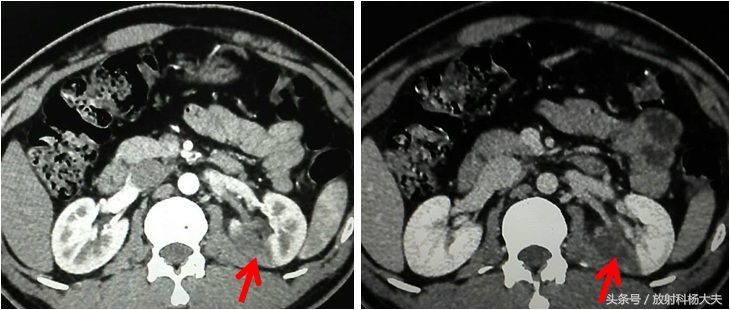

可以看到下图,增强扫描可以看到楔形的低强化区,累及到了肾脏的皮质和髓质,相应区域肾静脉属支也充盈的晚。

看到这些表现,只能想到两种情况。第一种可能是肾盂肾炎,多见于女性,除了肾脏改变,还有肾盂壁增厚,而且肾实质的强化程度不会这么低。第二种可能是:肾梗死。发生在某个小分支动脉因为各种原因堵住了,相应区域的肾实质因为没有血供而发生了坏死。

幸运的是,这位年轻大夫的梗死范围不大,不幸的,已经三天了,这块梗死的肾区域,将来会失去功能。